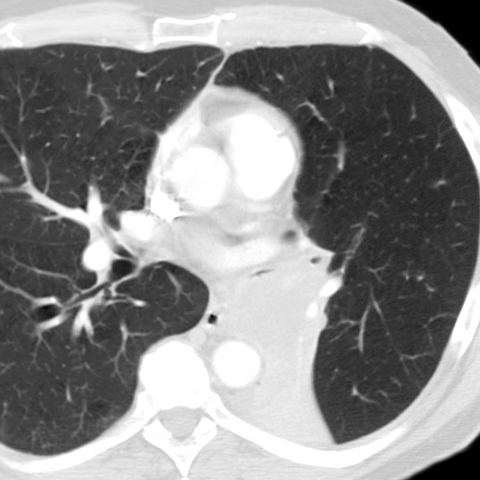

LLL Atelectasis [4 of 4]